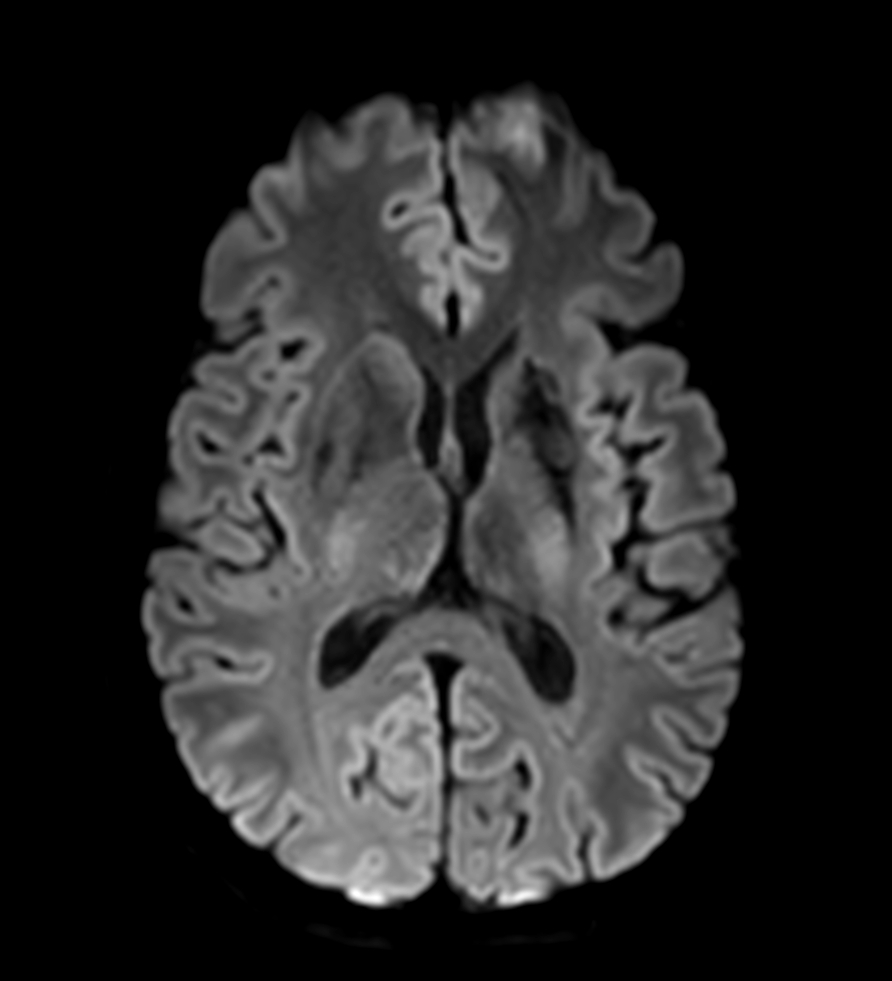

DWI (b1000)

DWI (ADC)